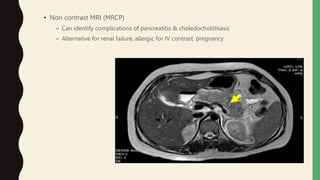

• Non contrast MRI (MRCP)

– Can identify complications of pancreatitis & choledocholithiasis

– Alternative for renal failure, allergic for IV contrast, pregnancy